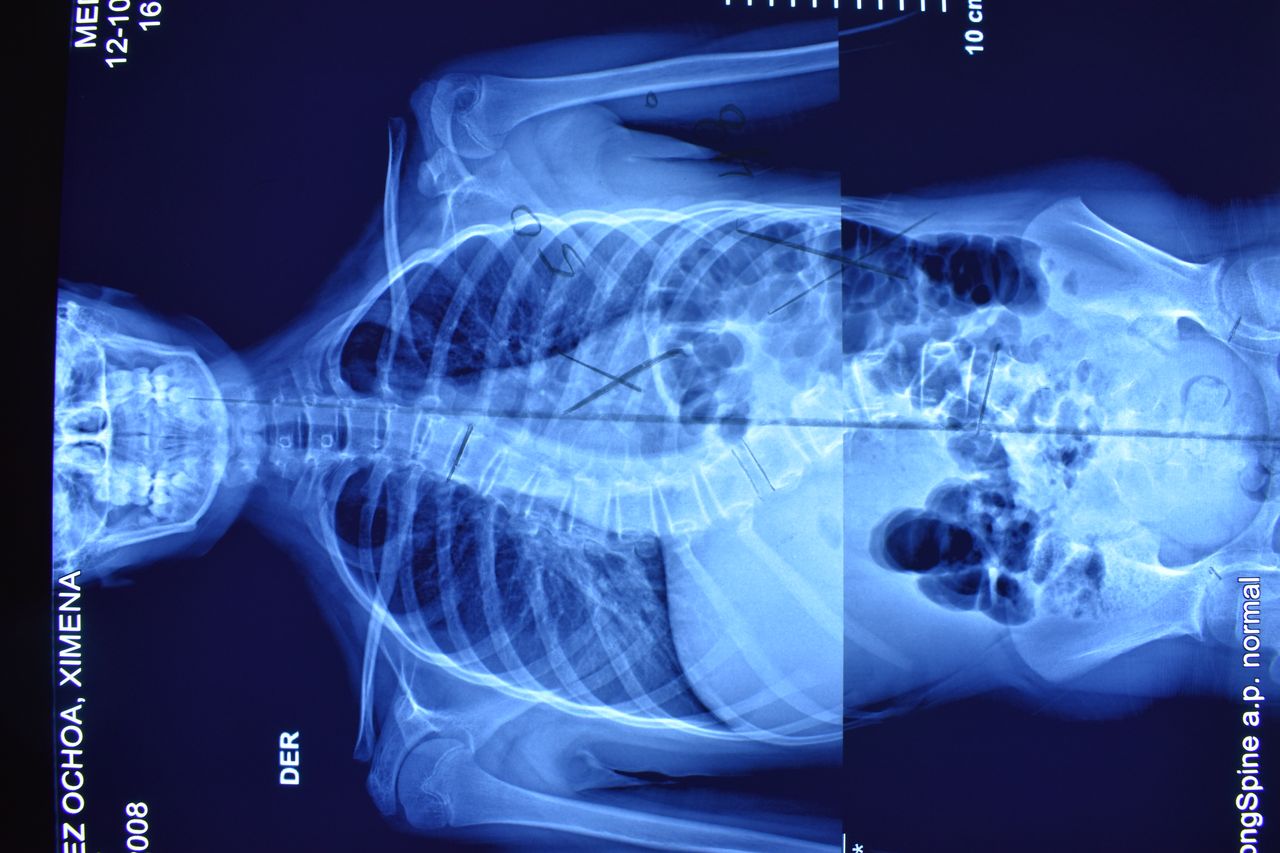

• Cirugía de columna

• Fusiones vertebrales amplias por vía anterior

• Fusiones vertebrales por vía posterior